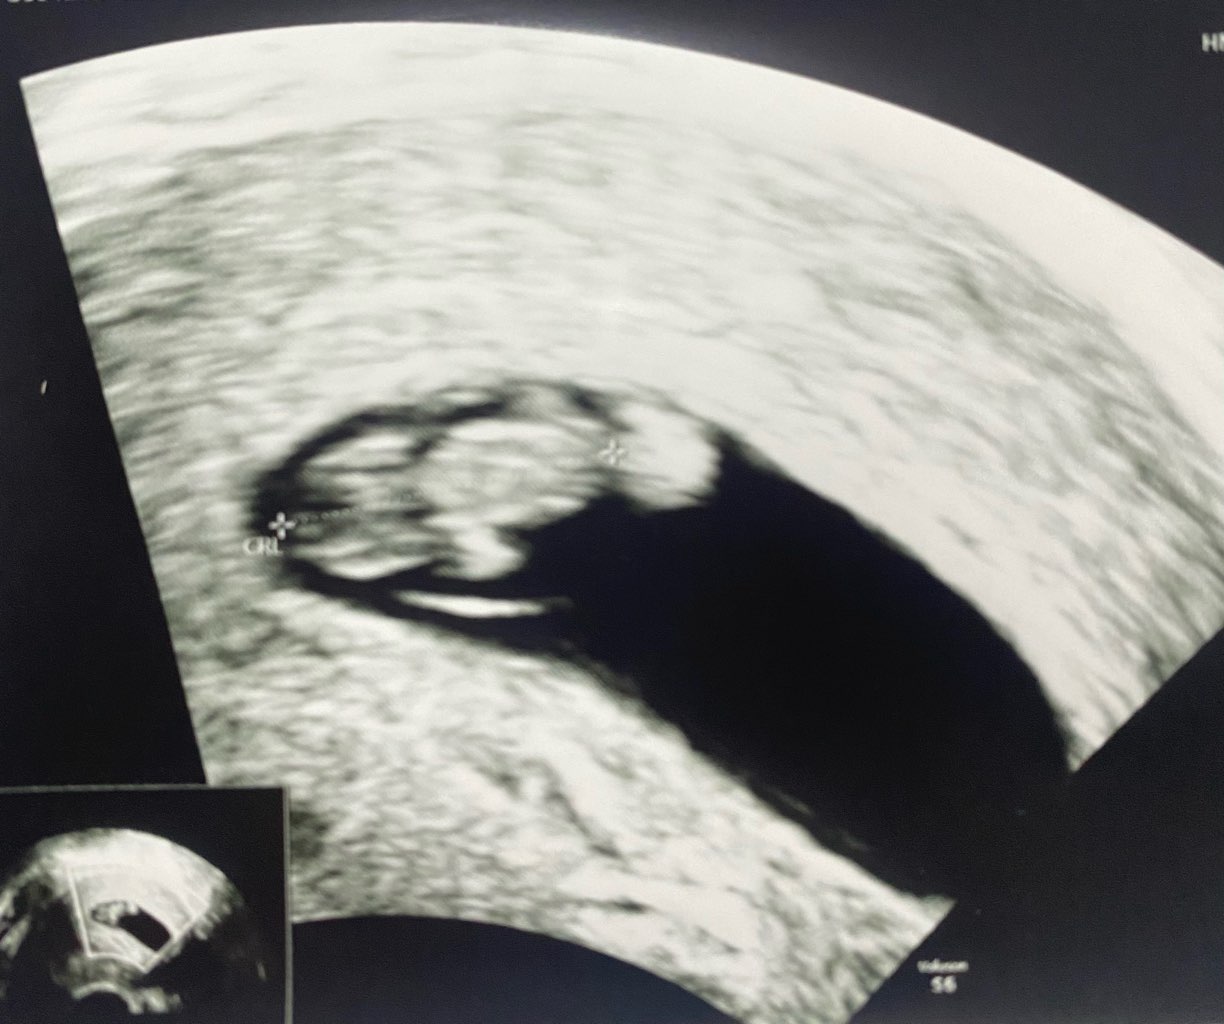

jest dzidzia, jest serduszko. Z USG wychodzi 7+6 a z om jest 8+1. Zarodeczek 1,49 wygląd kurczaczka. Serducho 134/min.

Zmartwił mnie tylko krwiak podkosmowkowy ale za dwa tygodnie mam wizytę i bedziemy kontrolować. Póki co sporo badań z krwi. Dostałam już skierowanie na prenatalne się zapisać w specjalistyczne miejsce i na pappa. Mam za darmo z racji wieku.